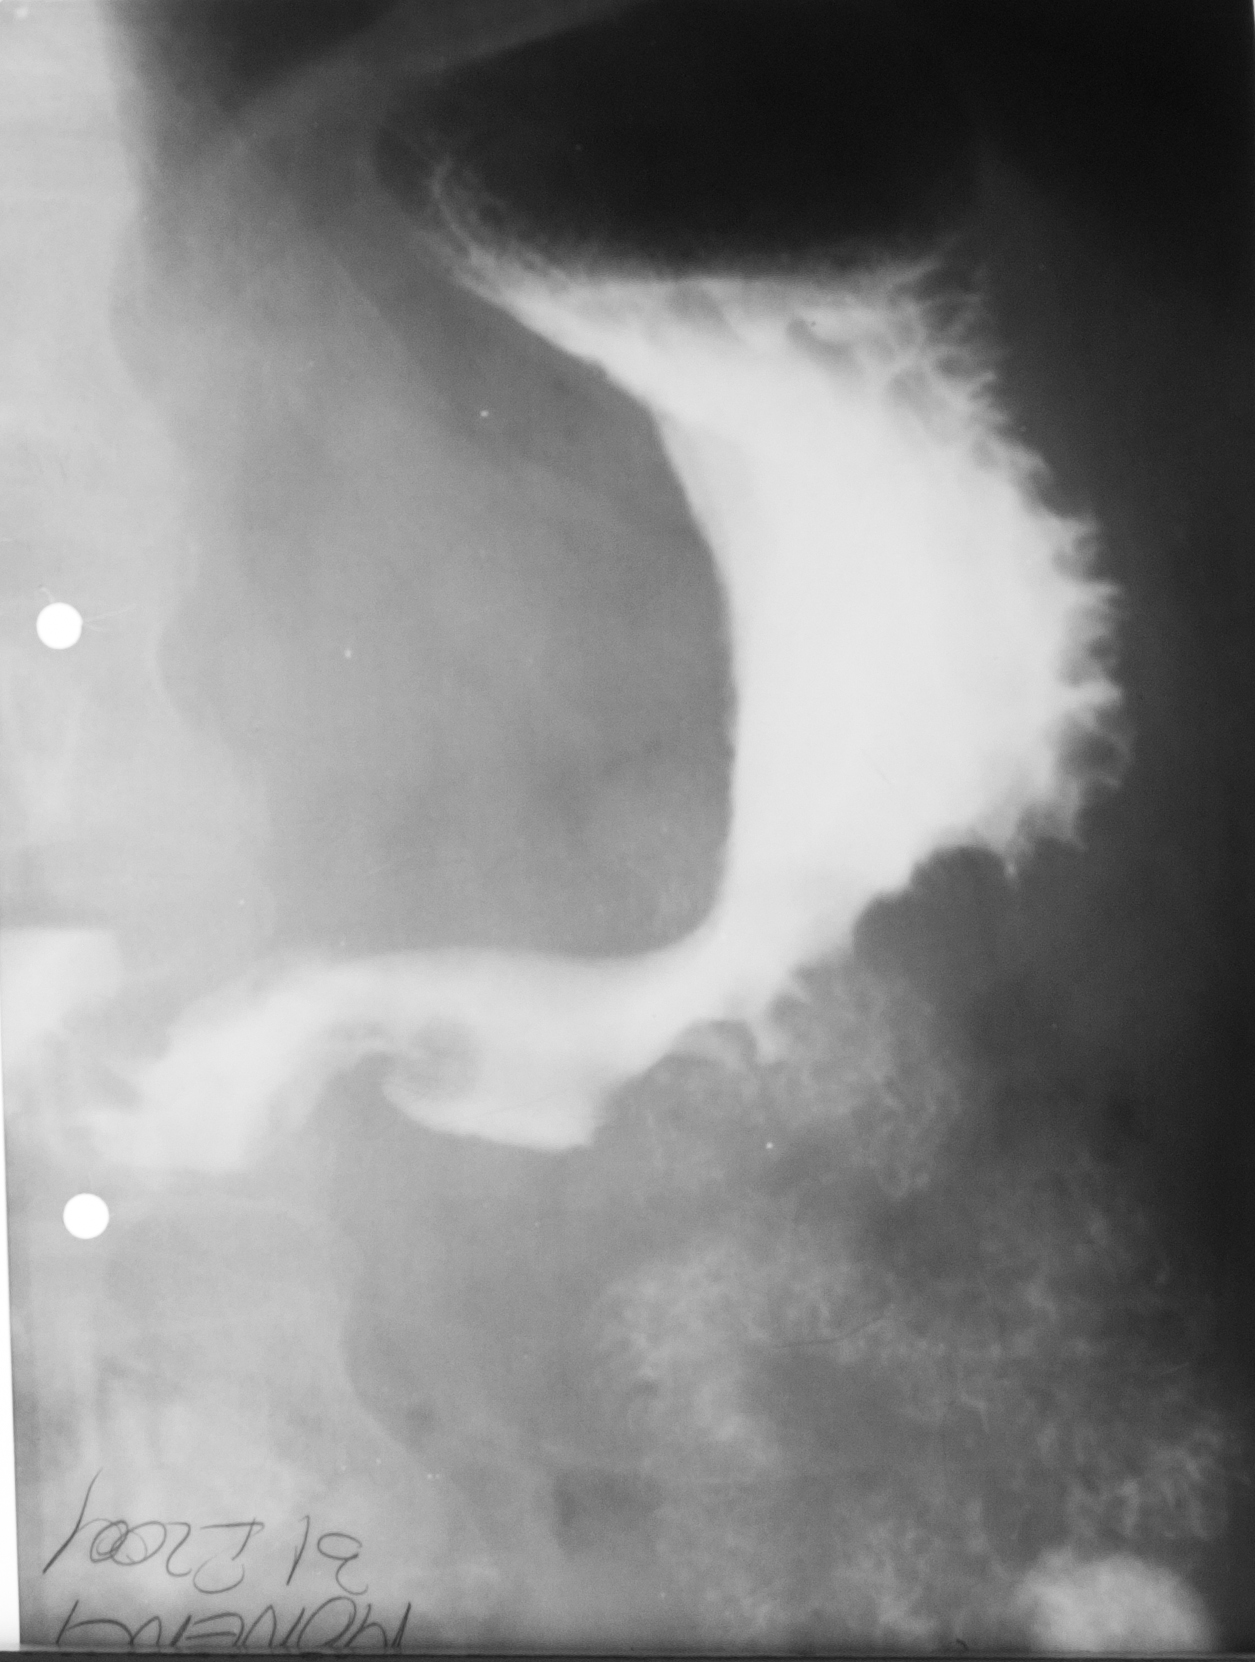

STOMAC NORMOTON(aspectul radiologic)

Tranzitul baritat al stomacului.Aspectul stomacului cu substanță de contrast:forma literei J cu fornix,corp,antru,canal piloric + bulb duodenal,D2(partea descendentă a duodenului

STOMAC ORIENTALIZAT/HIPERTON (aspect radiologic normal)

Stomacul hiperton este caracteristic persoanelor scurte și grase

STOMAC ALUNGIT (aspect radiologic normal)

Stomac alungit cu polul inferior aproape de nivelul crestei iliace.Este caracteristic persoanelor longiline

STOMAC DILATAT

Stomac destins cu substanță de contrast cu polul inferior aflat în micul bazin

Stomac dilatat cu mult lichid de secreție și stază gastrică

: NIȘA BENIGNĂ

Tranzit baritat la nivelul stomacului..La nivelul curburii mici se observă o imagine de adiție mai mult adâncă decât lată,cu pliuri de mucoasă ce converg spre zona respectivă

NIȘĂ BENIGNĂ

Nișă benignă mai mult adâncă decât lată,tot la nivelul micii curburi